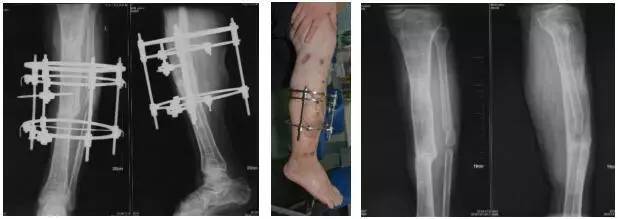

予清创截骨,Ilizarov外固定架固定

术后1年余,骨折愈合,拆除外固定架。恢复功能。